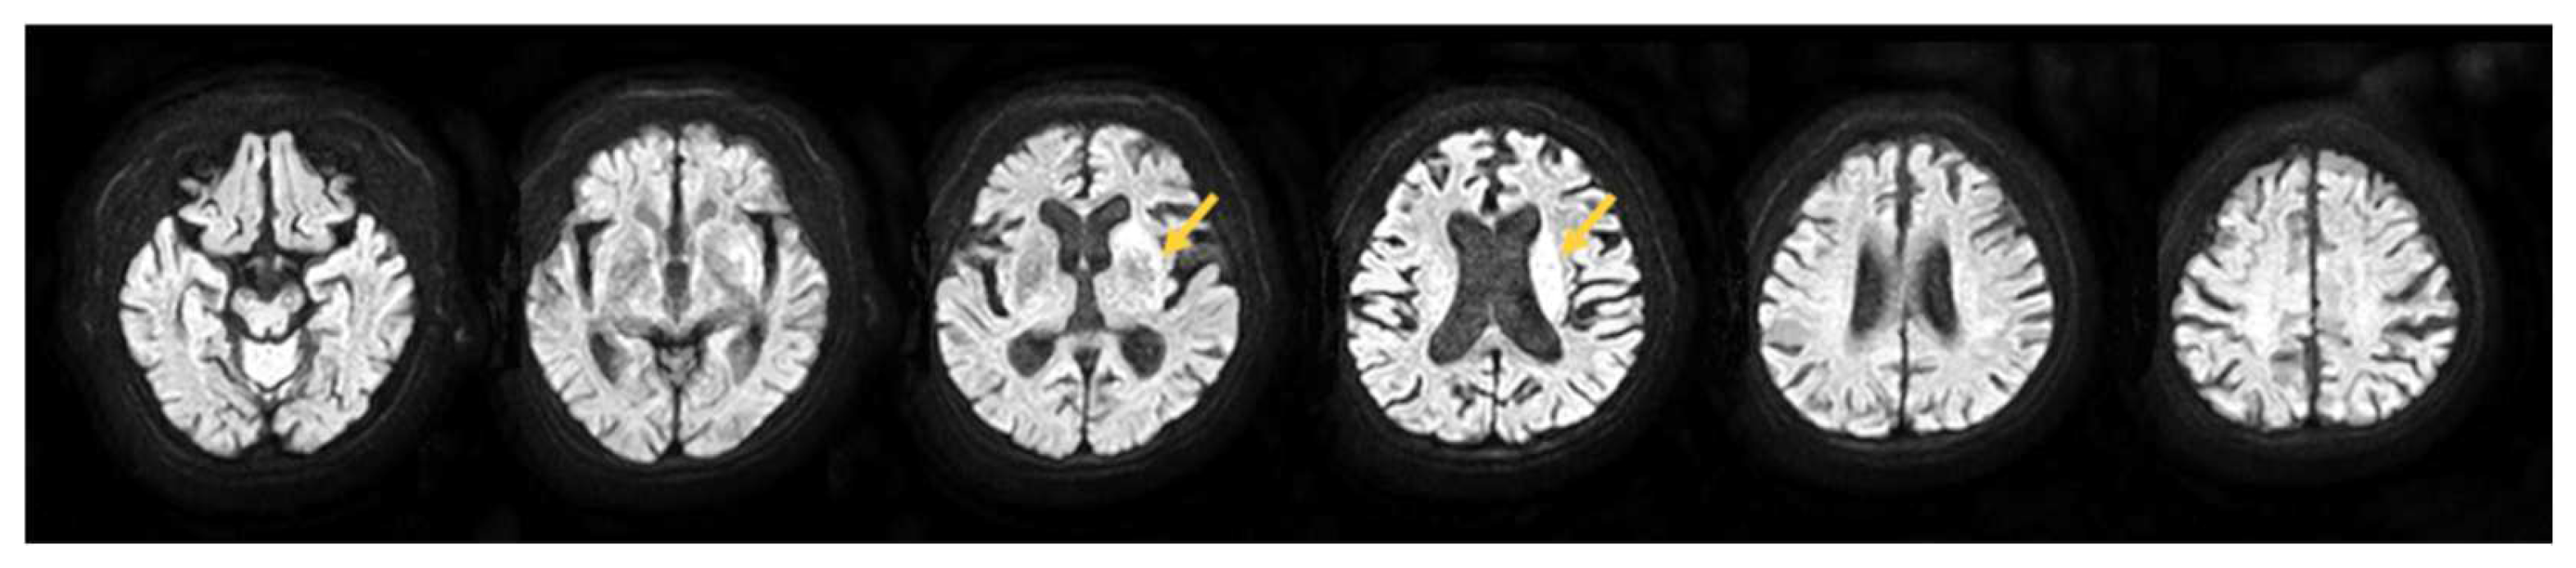

2.1. Participant